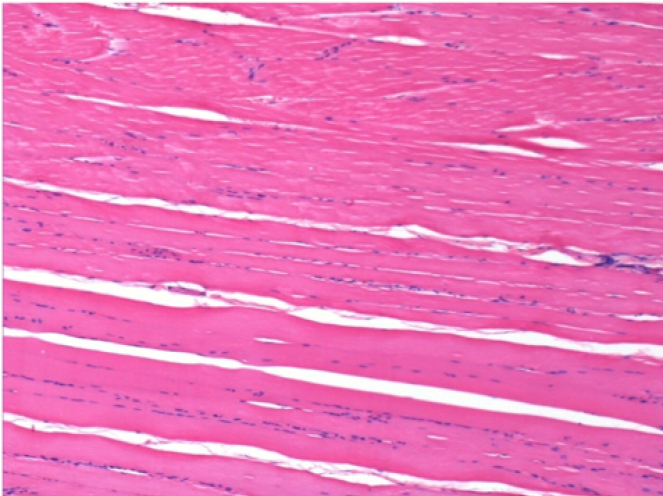

7 місяців (210 днів) після ін'єкції 0,1 мл Ендопіл в правий претибіальний м'яз.

Повна Restitutio ad integrum через 7 місяців